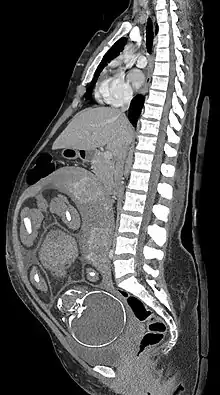

التصوير الطبي في الحمل

يمكن الاستطباب إلى التصوير الطبي أثناء الحمل بسبب مضاعفات الحمل أو الأمراض الواغلة في الحمل أو الرعاية الروتينية قبل الولادة.

- ينتج التصوير الشعاعي والتصوير المقطعي المحوسب والطب النووي درجة من التعرض للإشعاع المؤين، ولكن مع بعض الاستثناءات بجرعات الطاقة الممتصة أقل بكثير من ما يرتبط بضرر الجنين.[1] يشار إليها عندما لا يكون التصوير بالموجات فوق الصوتية أو التصوير بالرنين المغناطيسي متاحًا بسهولة أو غير ممكن للسؤال التشخيصي في متناول اليد.[1]

التصوير الشعاعي والطب النووي

آثار الجنين عن طريق جرعة الإشعاع

جرعات إشعاع الجنين بطريقة التصوير